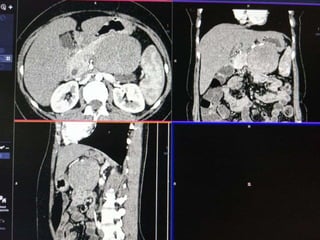

 55 yr old female patient

 Presented with complaints of lump abdomen and vague

abdominal discomfort

 Bowel habits normal with no other gastrointestinal complaints

CASE 2

DIFFERENTIALS

• Retroperitoneal sarcomas

Leiomyosarcoma

Undifferentiated liposarcoma

Malignant fibrous histiocytoma

• Exophytic Gastrointestinal stromal tumor